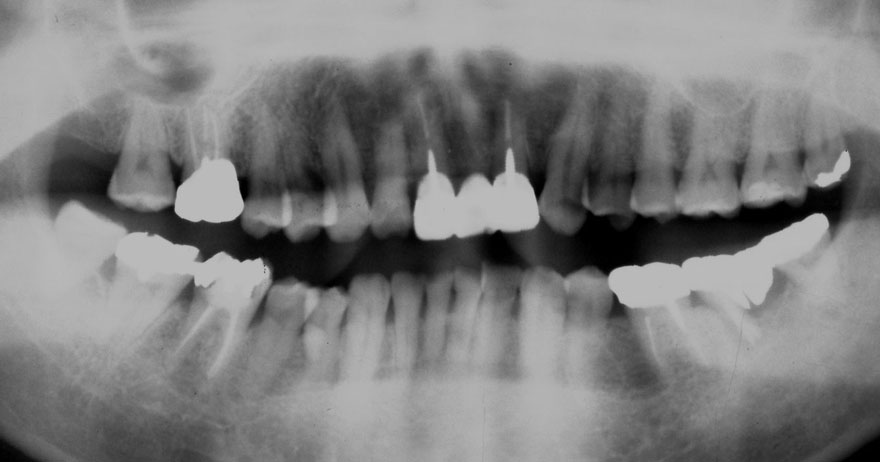

開始年齢 40代

初診時 40歳 女性 平均歯槽骨喪失量:3.14mm

32年後 72歳

平均歯槽骨喪失量:3.22mm

32年間喪失量:-0.08mm

年間喪失速度:-0.002mm

(ケア頻度:1.86ヵ月ごと)